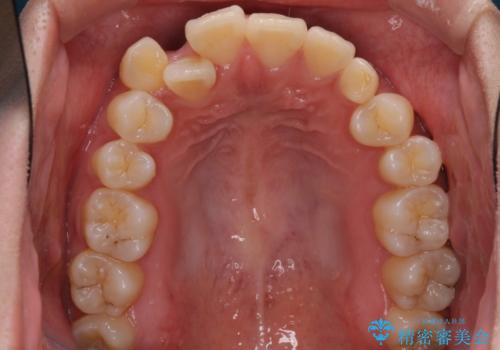

- 前歯のデコボコと残っている乳歯の部分へのインプラント治療を希望して来院された患者様です。

当初は目立たない上下裏側矯正を希望されていましたが、歯並びの悪さによる磨き残しが多く、歯肉炎が認められたため、より清潔な環境で治療を進められるインビザラインを選択することとしました。

また、インプラント治療については、インビザラインによる矯正治療中の最適なタイミングで治療を行い、治療期間の短縮を図ることとしました。

インプラントは、治療期間を短くすることが可能な、ストローマン社のSLActiveを使用することとしました。

前歯のデコボコが強かったため、上の奥歯を後方に動かす量が多くなり、結果として2年以上の治療期間を擁することとなりました。

インプラント治療は当初の狙い通り、矯正治療期間中に行い、スムーズに処置を進めることができました。

歯並びが整ったことで治療前に認められた歯肉炎は全くなくなり、患者様には大変満足していただきました。